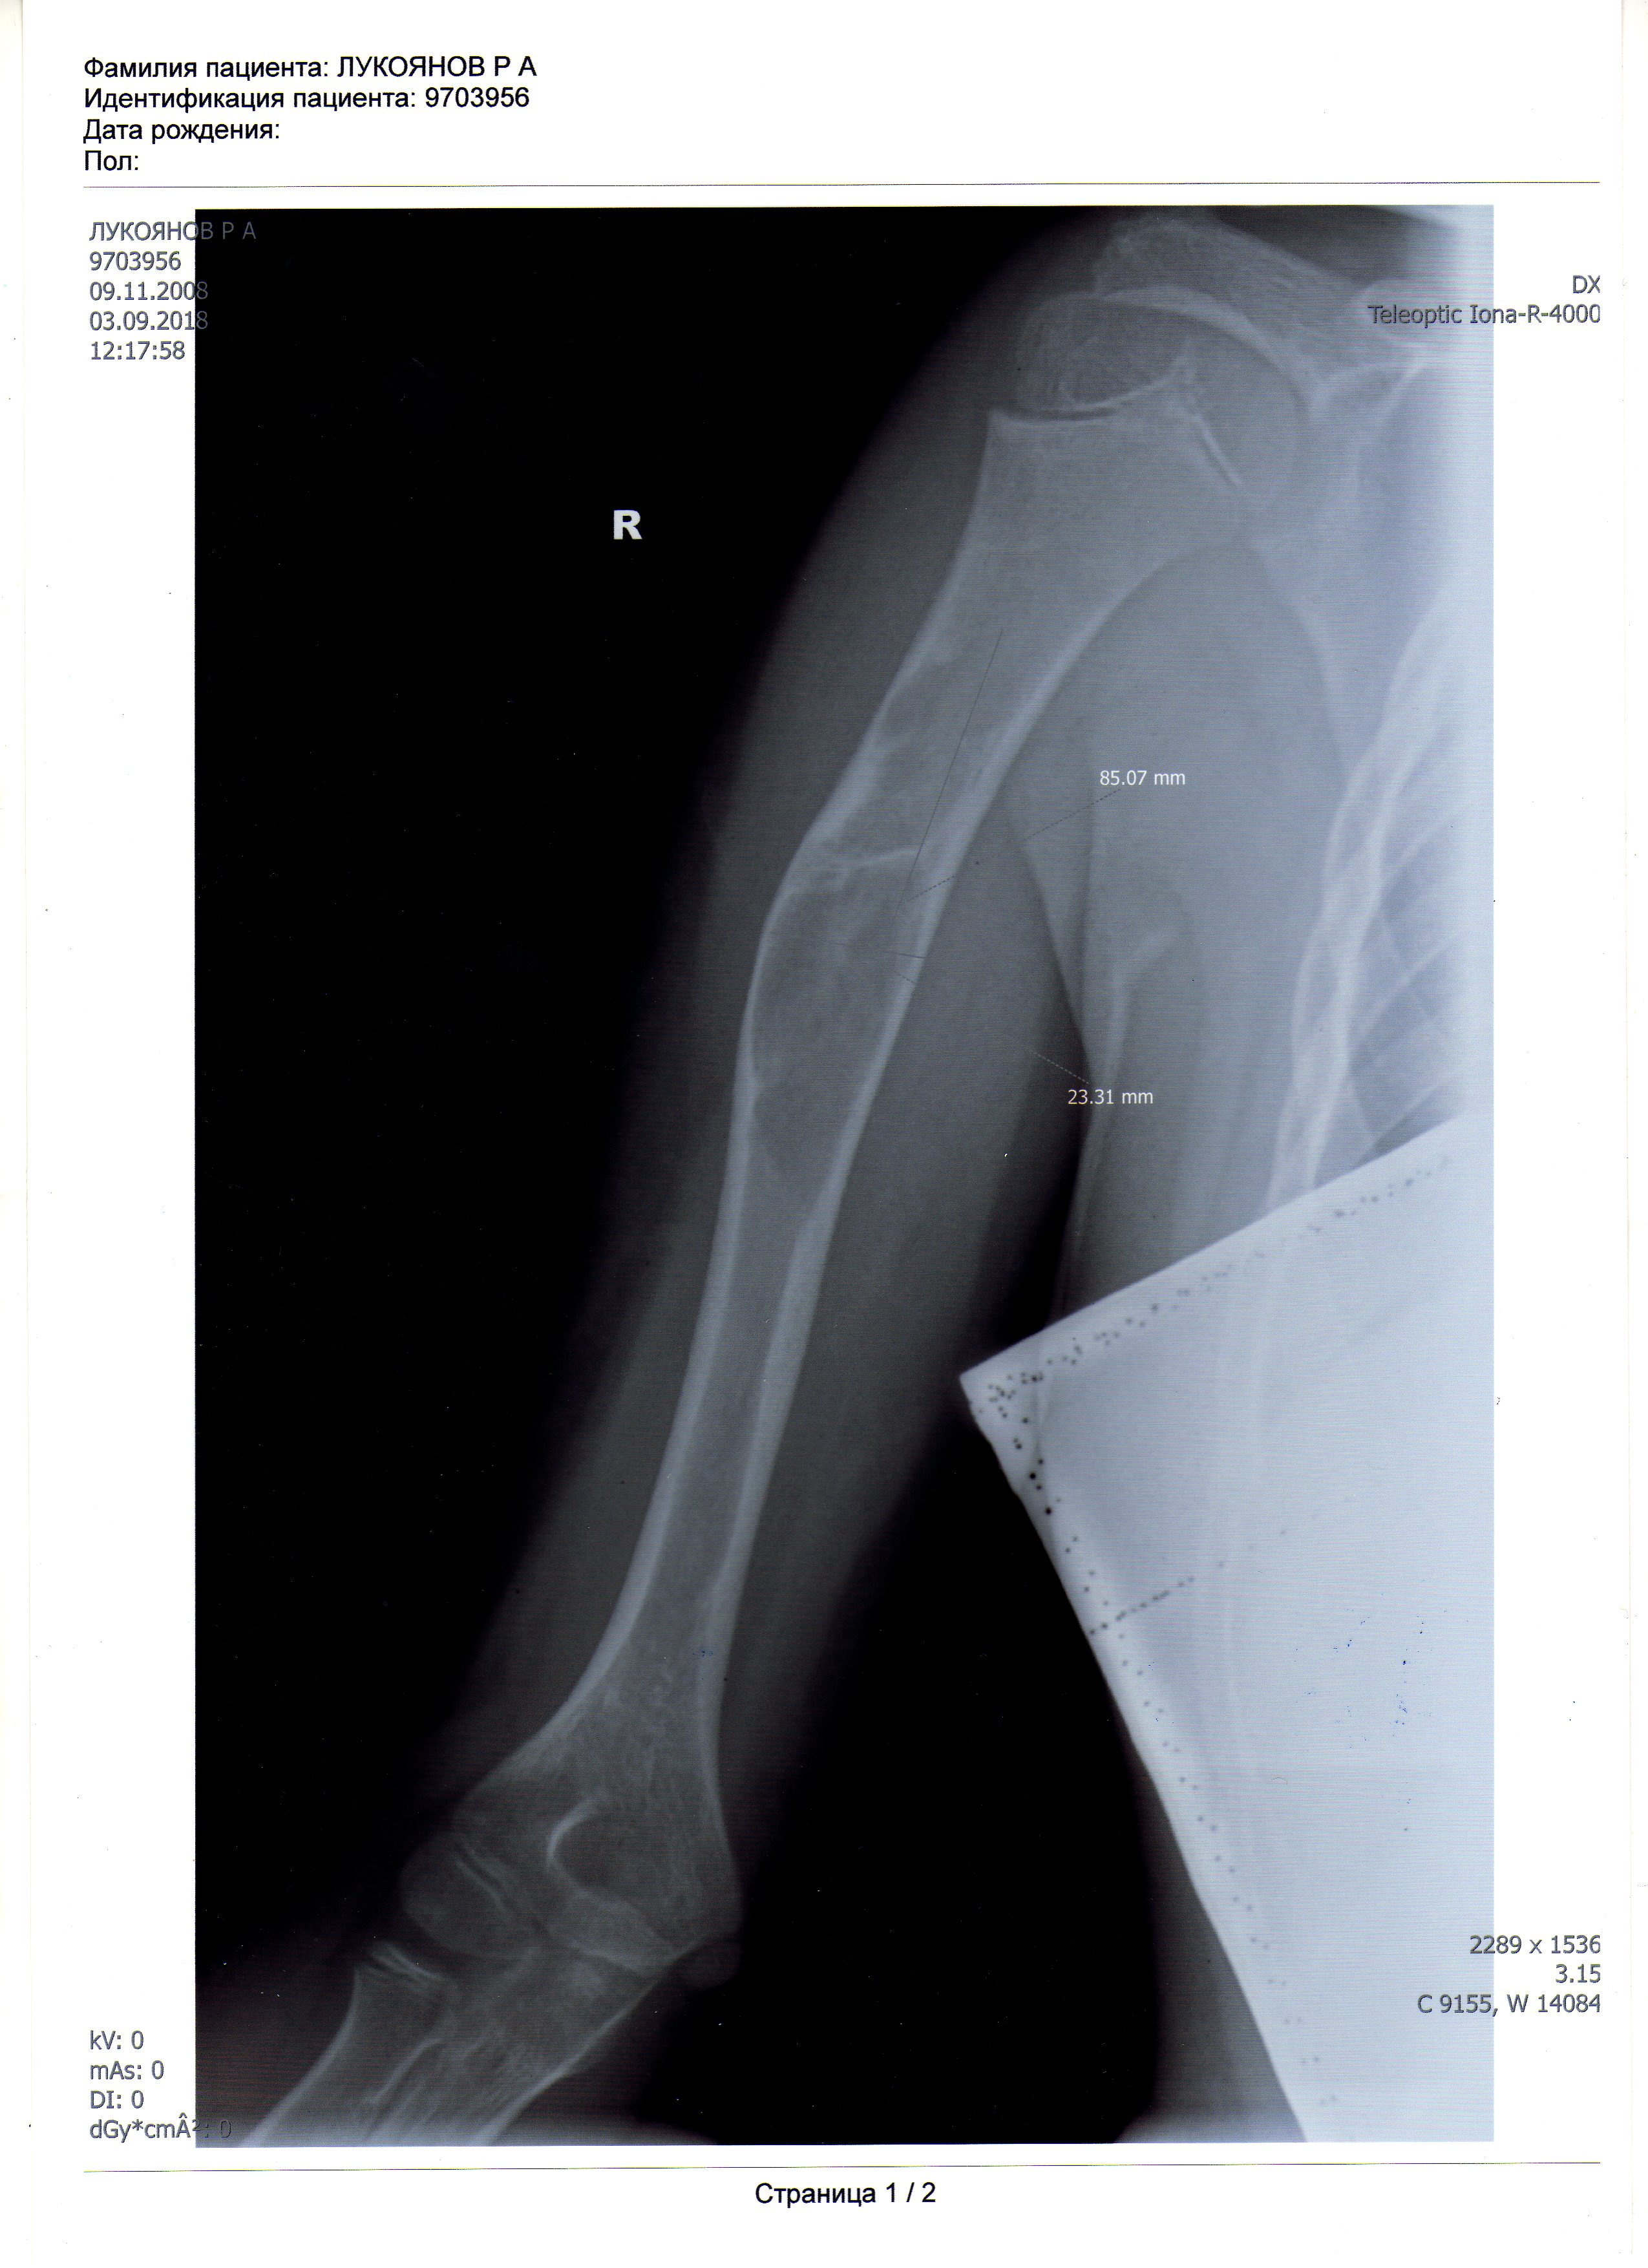

Меня зовут Маргарита, мне 29 лет, я мать-одиночка из малообеспеченной семьи с мамой -инвалидом I группы на руках. Моему сыну Рудольфу 10 лет. Ему поставили диагноз: костная киста правой плечевой кости, выраженный болевой синдром. Нужна операция. К сожалению, продать мне нечего, обращалась в разные фонды, но помощи не получила. Собрать 40 тыс. грн. я никак не смогу. Помогите, пожалуйста, кто чем может! Будем вам очень благодарны!